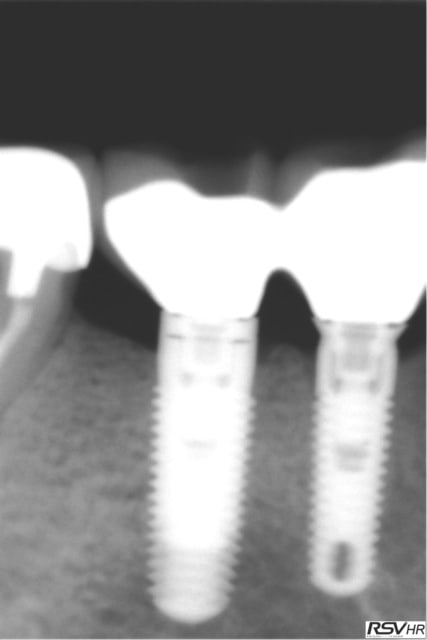

Pour Cyanolit des photos de swish plus pose en 2014

MEG1 MEG2 CH1 CH2et swiw + ric en 2015 (swish d'implant direct

2 radios de 2 zimmer SPAT1 en 2010 pose et provisoire

et SPAT2 2015 comportement actuel